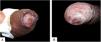

Case reportsTable 1 describes the five patients with ACL with genital lesions treated between 2007 and 2019, who comprised the entire series of ACL with genital involvement observed in this institution during this period. The mean age of the patients was 43 years. Among those with DL, a large number of skin lesions were observed, with a mean of 51 lesions. The mean time from the onset of genital lesions until diagnosis was 5.6 months. The diagnosis was confirmed by finding the parasites in one or more of the following tests: direct examination (imprint or scraping), histopathological examination, culture, and/or polymerase chain reaction (PCR) performed in biopsies of the skin lesions. All patients presented upper airway and digestive tract (UADT) mucosal involvement and were tested for HIV and syphilis in order to rule out co-infection. Four of these patients had DL and two were HIV-positive. The glans was the most affected site (Fig. 1). Four patients had painless penile ulcers, except for patient 3, who had penile edema and multiple painful lesions on the foreskin that prevented the exposure of the glans. After treatment, foreskin retraction allowed observation of the lesions on the glans (Fig. 2). Patient five (Fig. 3) presented an ulceration in the body of the penis and another in the scrotum.